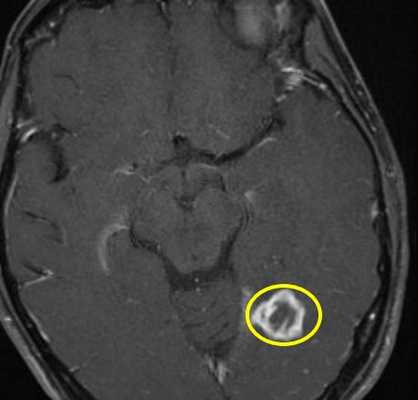

Инфекции быстро прогрессируют, особенно токсоплазмоз. При МРТ виден выраженный отек вокруг очага. Контрастируется при МРТ токсоплазмоз обычно по кольцевому типу.

МРТ головного мозга. Т2-взвешенная аксиальная МРТ. Токсоплазмоз.

Лимфома также контрастируется на МРТ по кольцевому типу, но гипоинтенсивна на Т2-взвешенных МРТ головного мозга. По локализации лимфома чаще располагается перивентрикулярно, в то время как очаги токсоплазмоза в области базальных ганглиев и сопровождаются значительным отеком.

МРТ головного мозга. Т2-взвешенная аксиальная МРТ. Лимфома.

МРТ головного мозга с контрастированием. Туберкулема.